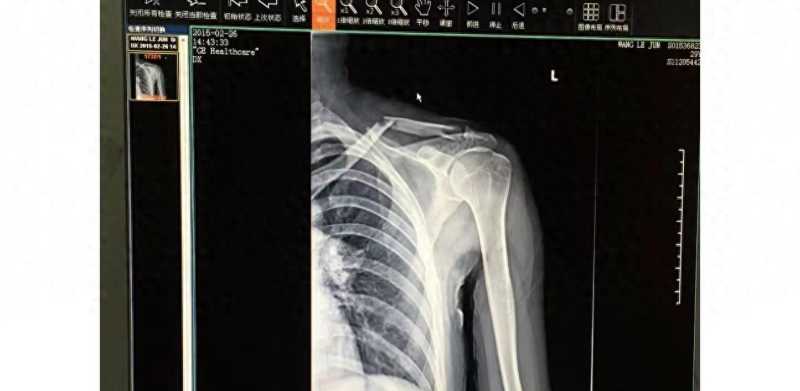

在他发布的第一张 X 光片中,撕裂的痕迹清晰可见,他声称这张照片是在撕裂后 12 小时内拍摄的。

据他透露,“明台”在拍摄过程中用身体摔断了锁骨。然后他痛苦地尖叫起来。情况非常严重,他的锁骨几乎完全断裂。

医生建议不要进行保守治疗,因为这需要特殊设备和卧床休息。为了继续拍戏,他无奈接受了手术,一共插入了7根钢钉。